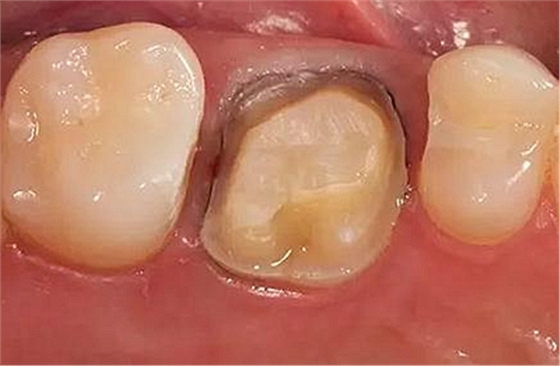

步驟1 原始狀況

16牙位牙齒牙合面觀.

牙齒經(jīng)過根管治療且充填修補(bǔ),需要重新修復(fù)。